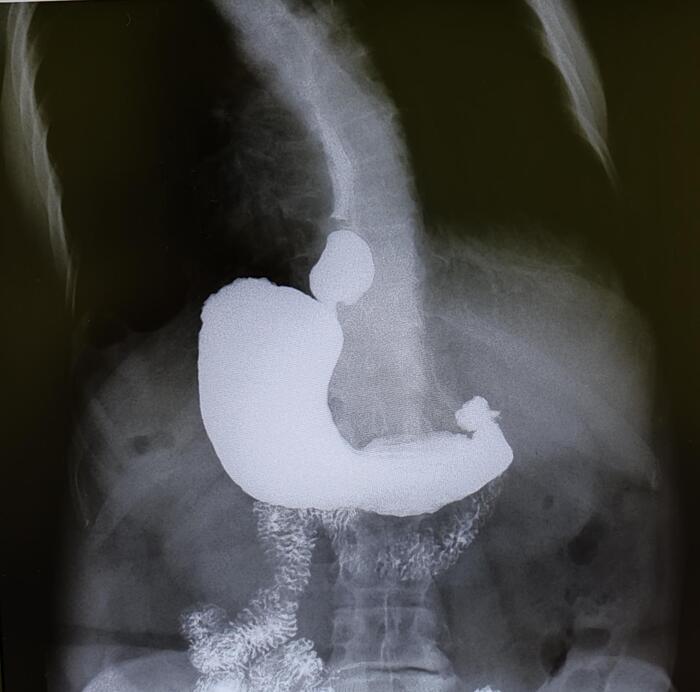

Дифференциальная диагностика

Эностоз необходимо дифференцировать с другими образованиями костной ткани, такими как:

Остеоид-остеома.

Остеобластные метастазы.

Склерозирующие дисплазии костей.

Для уточнения диагноза могут быть использованы дополнительные методы визуализации, такие как КТ или МРТ. В сомнительных случаях может потребоваться биопсия.

Варианты эностозов на КТ И МРТ.